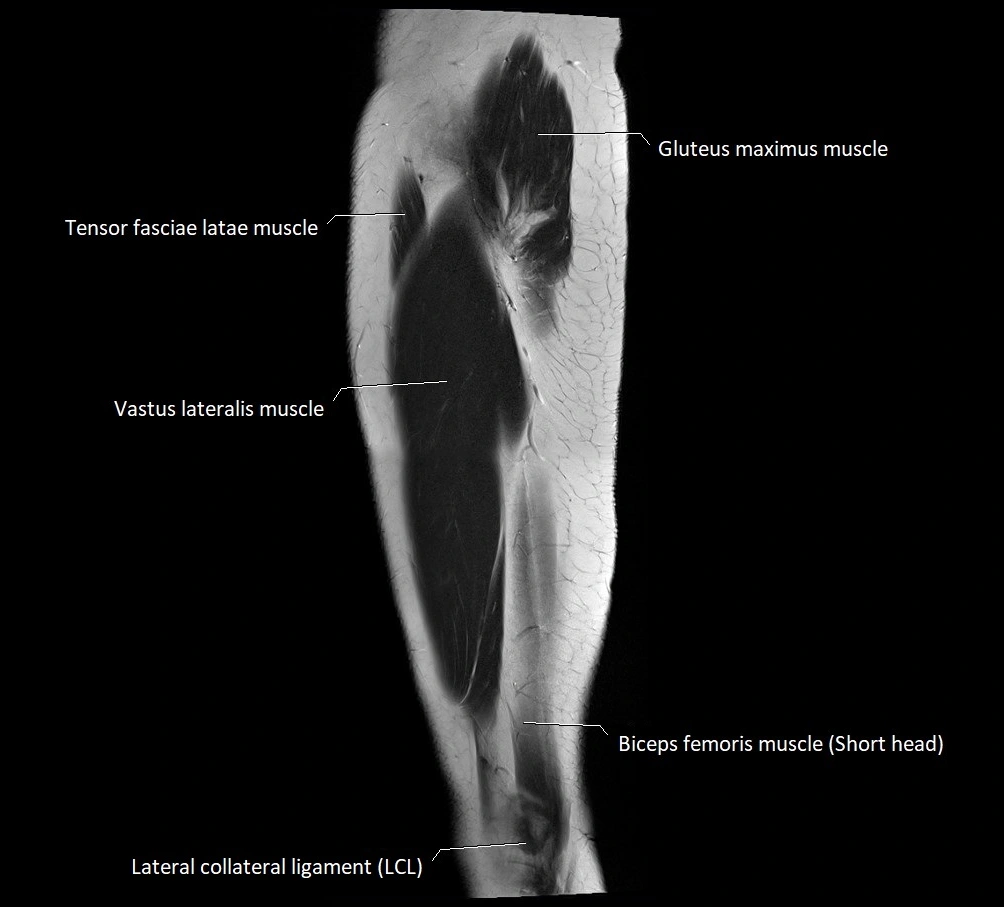

- Biceps femoris muscle (Short head)

- Gluteus maximus muscle

- Lateral collateral ligament

- Tensor fasciae latae muscle

- Vastus lateralis muscle